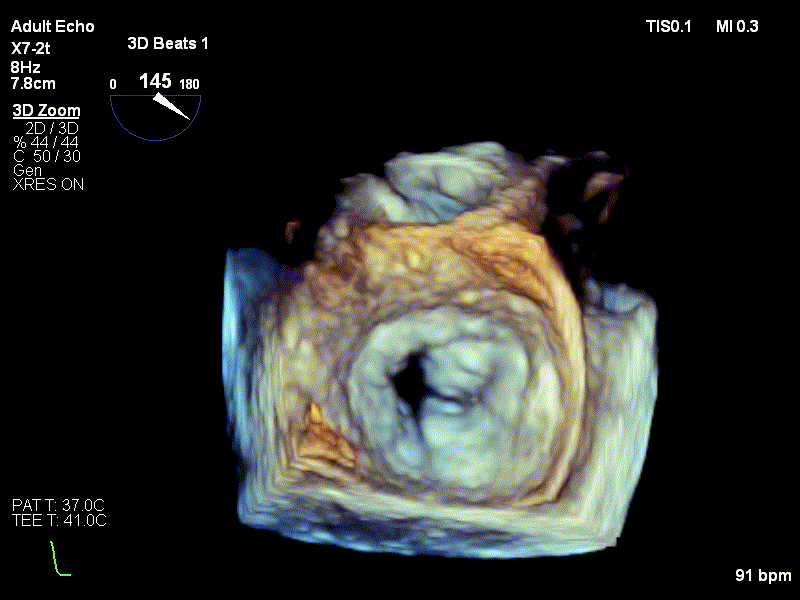

Diagnosticul de stenoză mitrală strânsă degenerativă a fost stabilit pe baza examenului ecocardiografic, realizat de dr. Irina Macovei-Dorobanțu, medicul cardiolog care s-a ocupat de pacienta pe toată durata spitalizării.

1. Imagine ecografie transesofagiană valva mitrală cu calcificări importante la nivelul cuspelor și al inelului, cu mobilitate limitată a cuspelor

3. Ecografie 3D valvă mitrală cu calcificări severe la nivelul cuspelor și al inelului, cu mobilitate mult diminuată